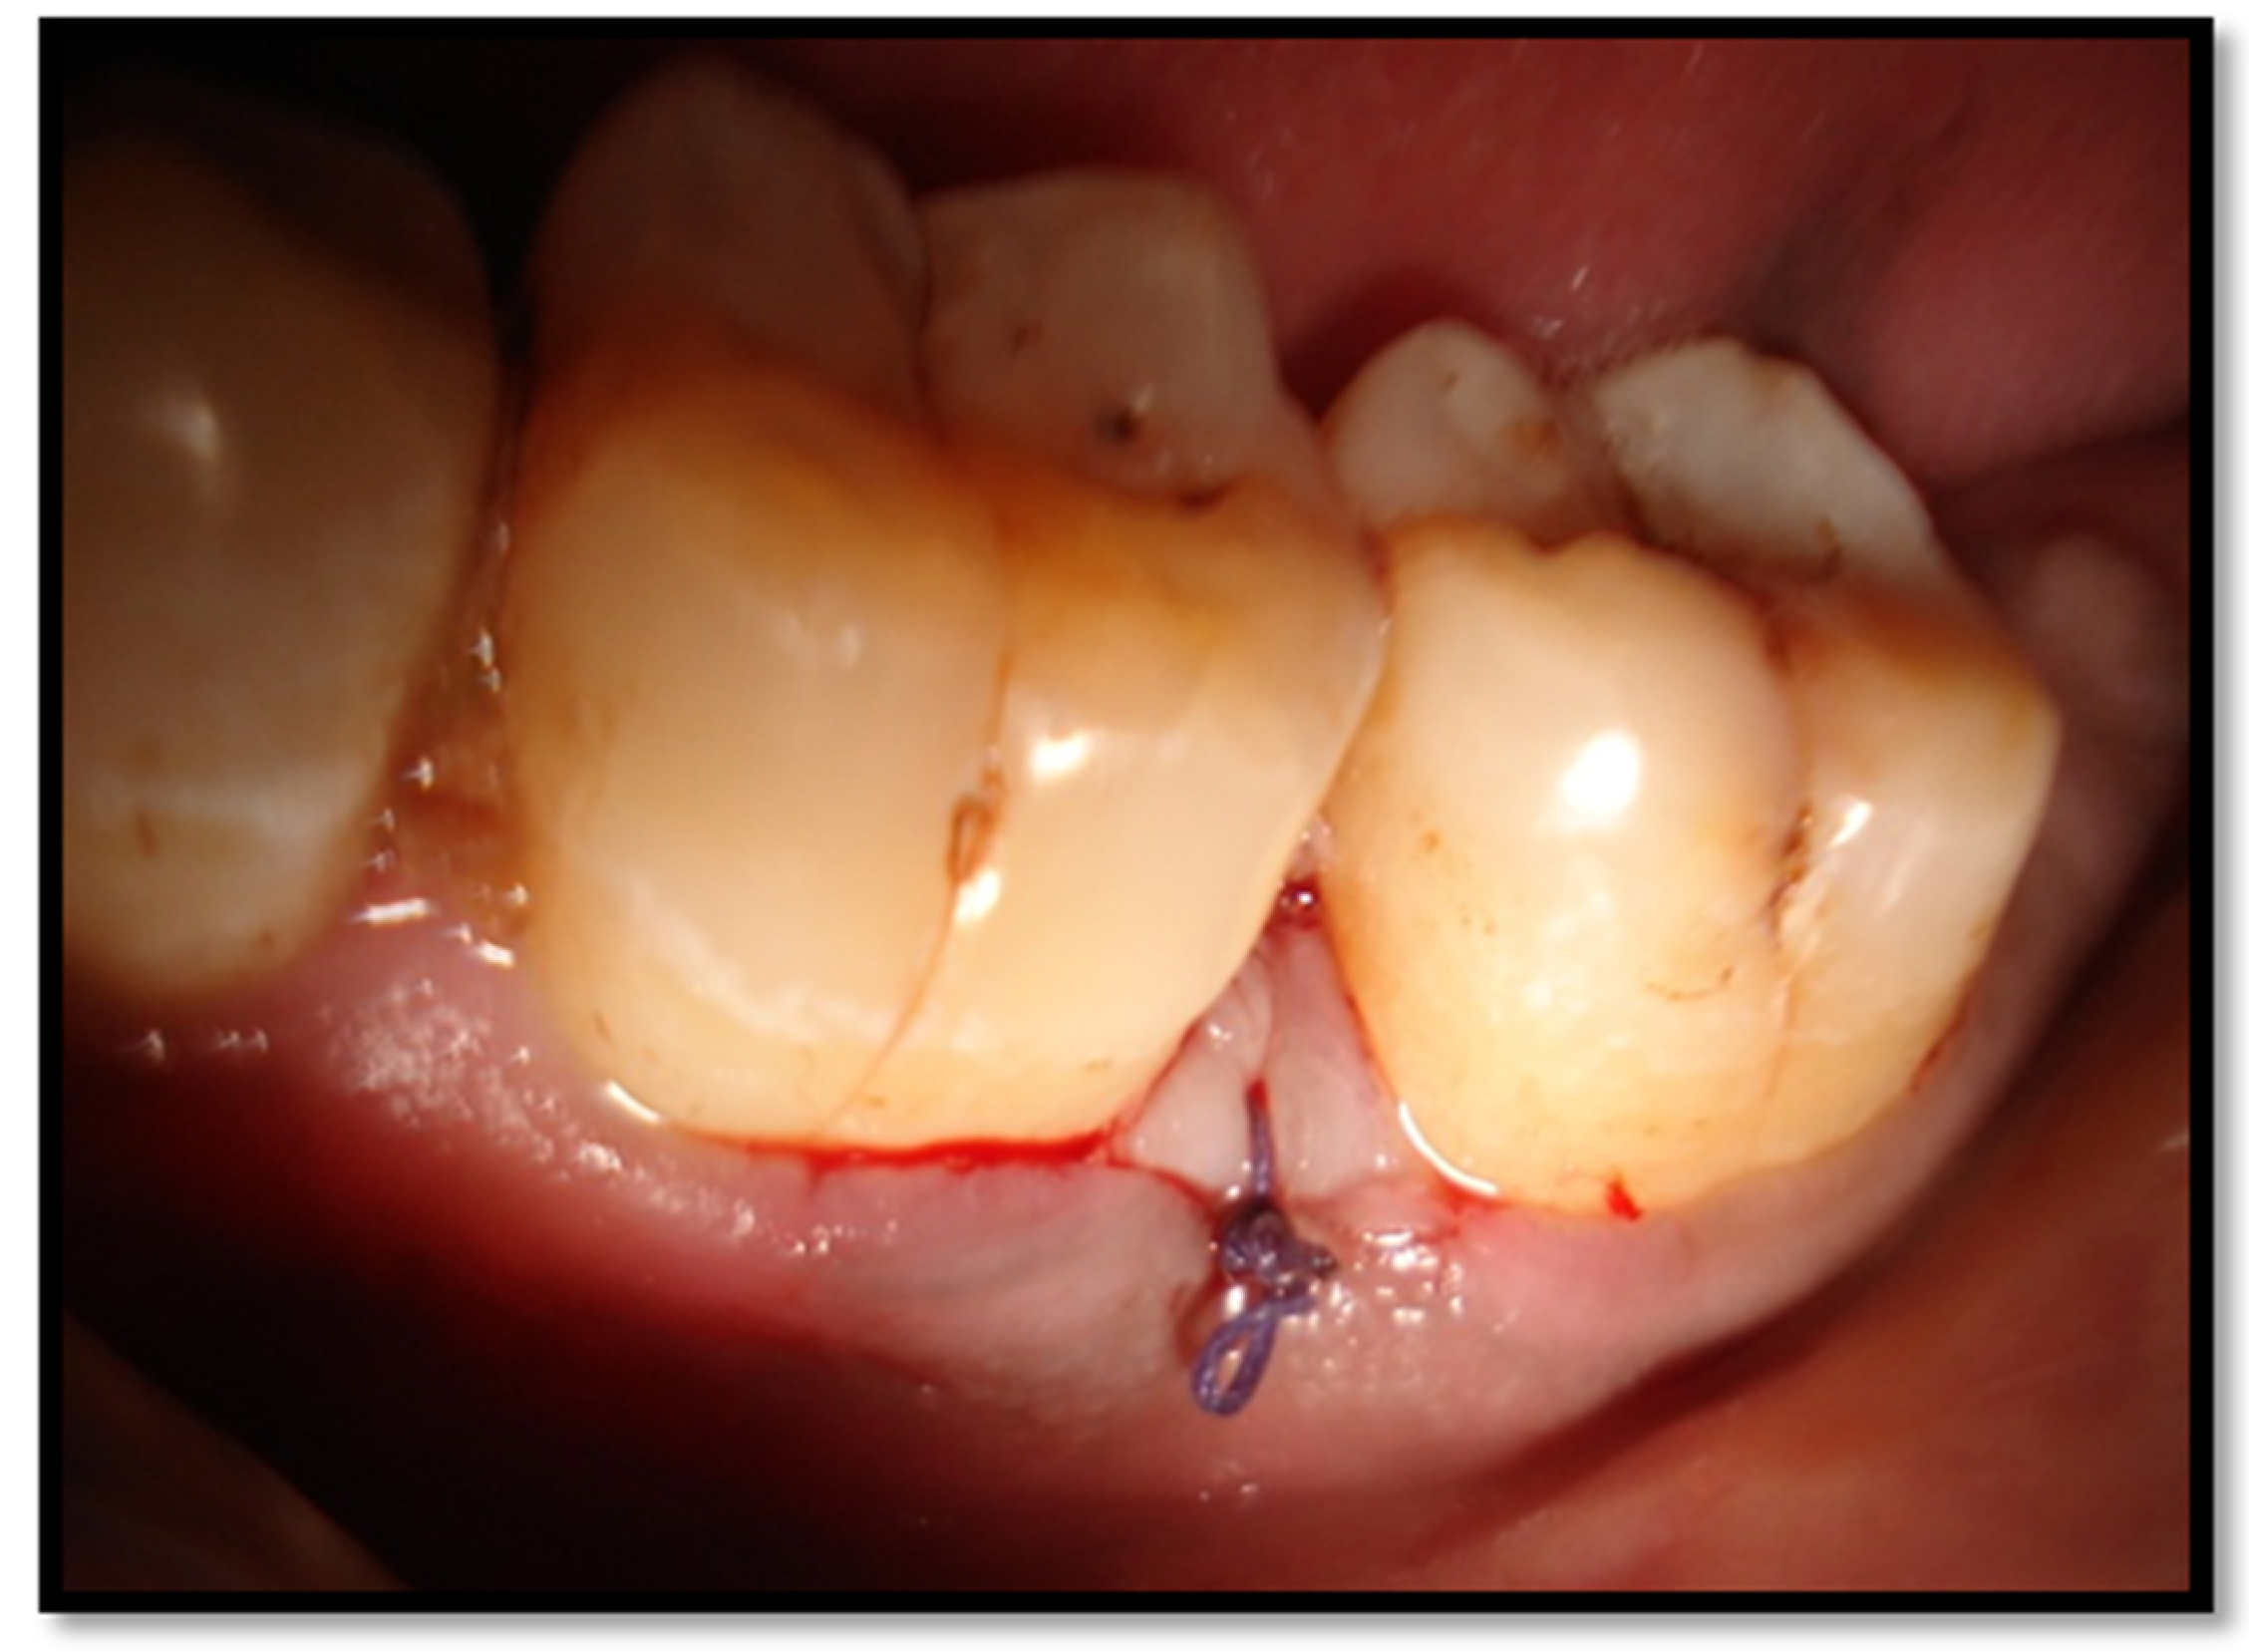

- Complete flap closure—no fibrin line in the interproximal area;

- Complete flap closure—fine fibrin line in the interproximal area;

- Complete flap closure—fibrin clot in the interproximal area;

- Incomplete flap closure—partial necrosis of the interproximal tissue;

- Incomplete flap closure—complete necrosis of the interproximal tissue.